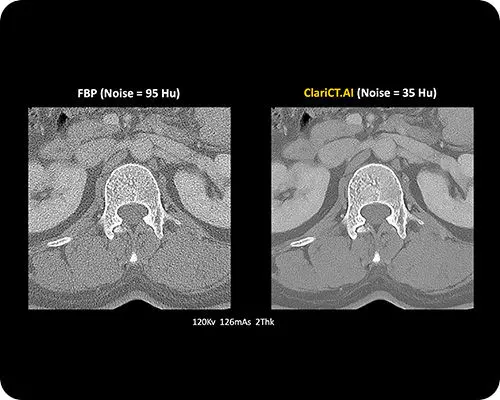

ClariCT.AI

ClariCT.AI es una solución de posprocesamiento basada en deep learning que mejora significativamente la calidad de imagen de las tomografías computarizadas (TC), incluso cuando se utilizan protocolos de dosis ultra baja. Diseñada para ser vendor-neutral, puede integrarse con cualquier escáner y PACS, convirtiéndose en una solución versátil para hospitales que buscan eficiencia y sostenibilidad.

Reducción de ruido de imagen de hasta un 87 %, manteniendo detalles anatómicos y textura.